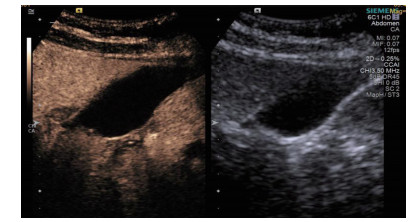

均采用塞丁格(Seldinger)技术置入引流管(图 4):穿刺穿刺点的选择①左侧卧位,超声确定胆囊床方位,取腋前线肋间或肋缘下进针; ②经肝的路径长度应大于2.0 cm胆囊穿刺点为中上部距离胆囊颈约1 /3的位置; ③穿刺路径上尽量避开大血管及大胆管结构; ④结合术前经肘静脉超声造影情况,避开胆囊穿孔部位及周边黏连组织。操作过程:由超声介入治疗组专业医师单人操作,为获得更自由的穿刺角度以及在穿刺过程中根据患者呼吸活动随时对进针角度进行调整,本组操作均未使用超声探头引导架。操作步骤①常规碘伏皮肤消毒,2%利多卡因局部麻醉至肝脏被膜。操作医师一手持超声探头,清晰显示进针入路,一手持18 G PTC穿刺针经皮经肝由胆囊床穿刺进入胆囊,拔出针芯,可见胆汁自行流出或用20 mL注射器回抽见胆汁。②沿针鞘置入导丝,超声探查见导丝进入胆囊,拔出针鞘。③扩张器扩张针道。④根据抽出胆汁的混浊程度,沿导丝置入合适型号的引流管,确定引流管通畅后拔出导丝,拉紧猪尾导管的外置固定线,使导管弯曲头牢固卷曲,形成内固定,皮肤缝线外固定引流管,双重固定更加有利于引流管留置于可靠位置,有效避免脱管。术后再次皮肤消毒,覆盖无菌贴膜。接引流袋。⑤术中及术后半h均予心电监测,术后常规送胆汁细菌培养,密切观察患者症状体征改善情况。

图 4 胆囊置管过程,导丝进入胆囊腔内(箭头处)